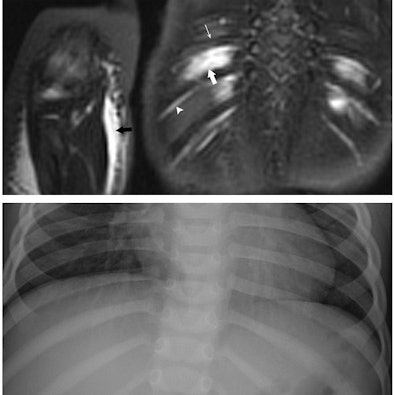

| Images are of a 17-month-old boy with suspected nonaccidental trauma. Coronal WB-STIR (top) of posterior chest wall and right elbow demonstrates edema of intercostal muscles (large arrow), but no fracture of adjacent ribs (thin arrow). Note normal hyperintense subcostal neurovascular bundle (arrowhead). There is diffuse subcutaneous edema of right antecubital fossa (black arrow) related to failed catheter placement. Corresponding RBS (bottom) corroborates absence of rib and elbow (not shown) fractures. Images courtesy of Dr. Peter Evangelista. |